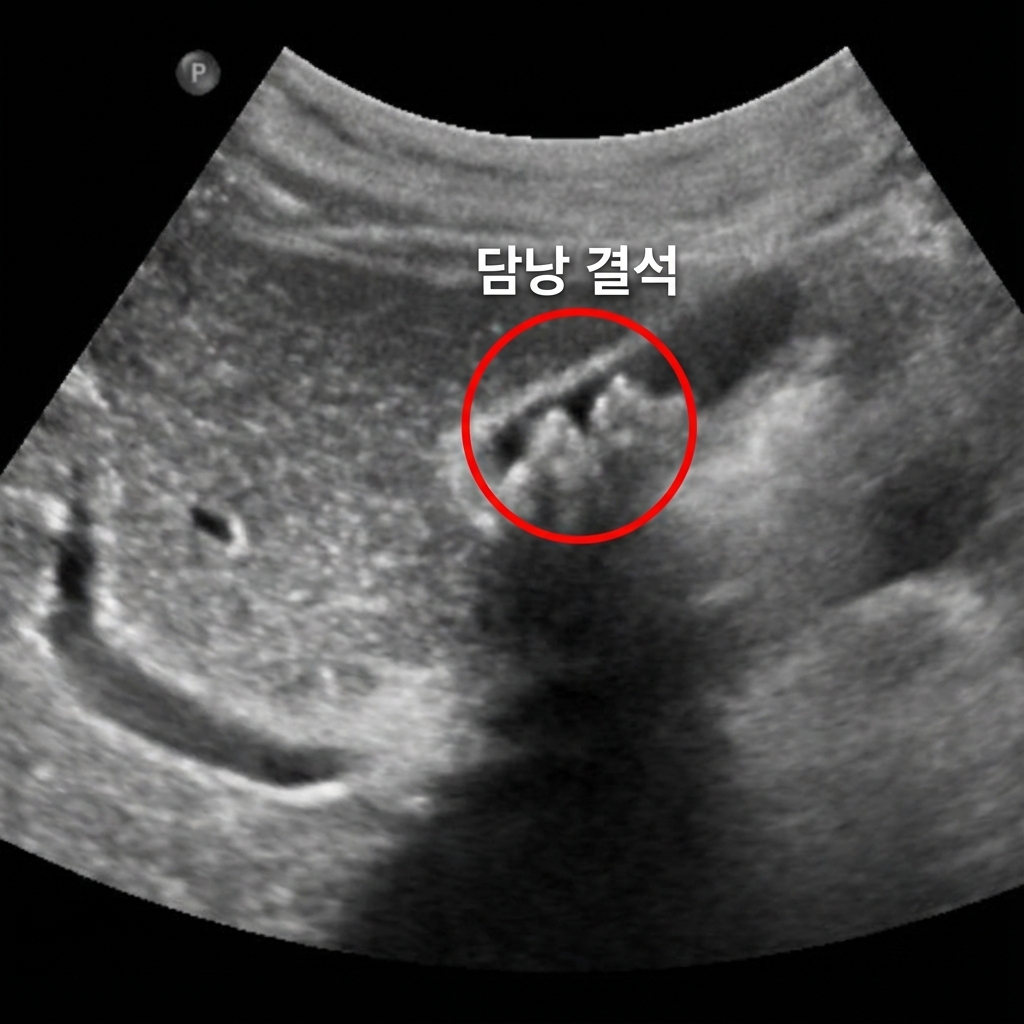

담낭·담도: 담석·담낭염

담낭 안에 둥글고 하얗게 보이며, 뒤에 그림자를 만드는 구조가 보이면 담석을 의심합니다. 담낭벽이 두꺼워지거나 주변 염증 소견이 동반되면 급성·만성 담낭염을 고려하게 되며, 담도 확장은 담도 결석·폐쇄 여부 평가에 중요합니다.